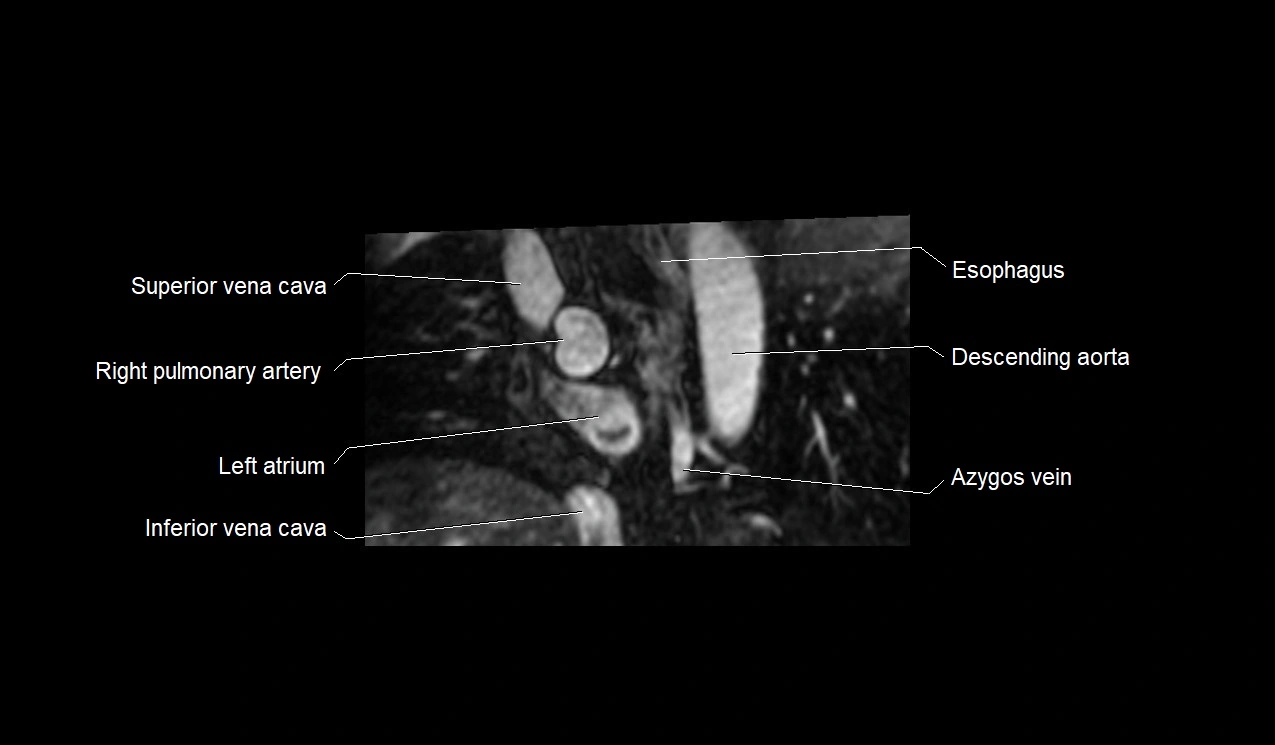

MRI image